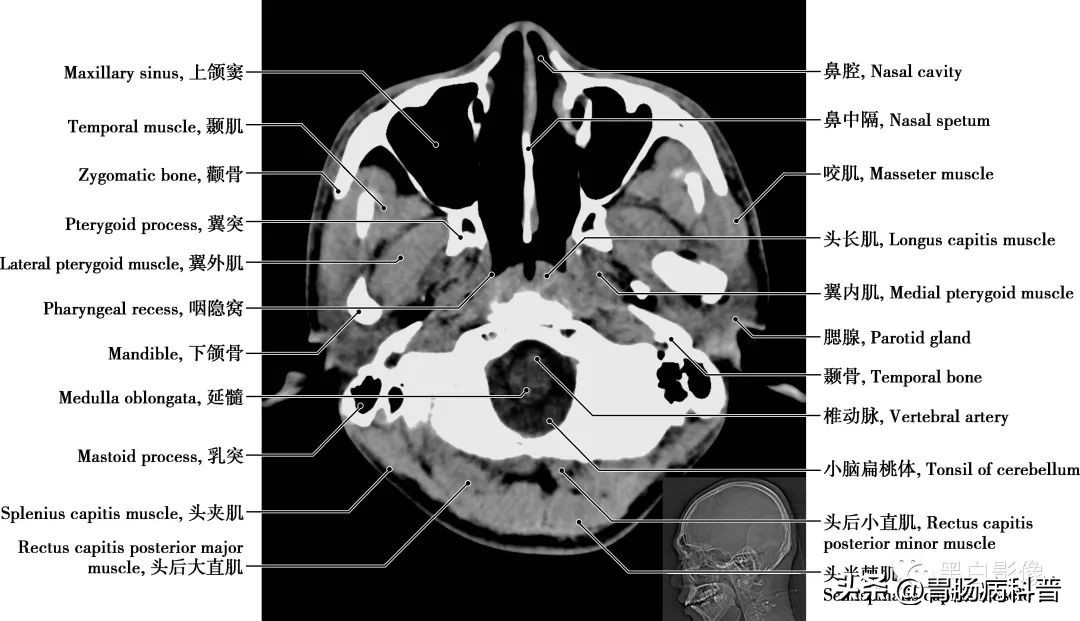

图1-1-20 经枕骨大孔轴位切面

小脑扁桃体 小脑下面靠小脑蚓两侧小脑半球的突起称小脑扁桃体。鼻中隔 把鼻腔分成左右两部分的组织,由骨、软骨和黏膜构成。鼻中隔骨结构由筛骨垂直板、犁骨和鼻中隔软骨共同构成,多偏向一侧。腮腺 最大的一对唾液腺,位于两侧面颊近耳垂处